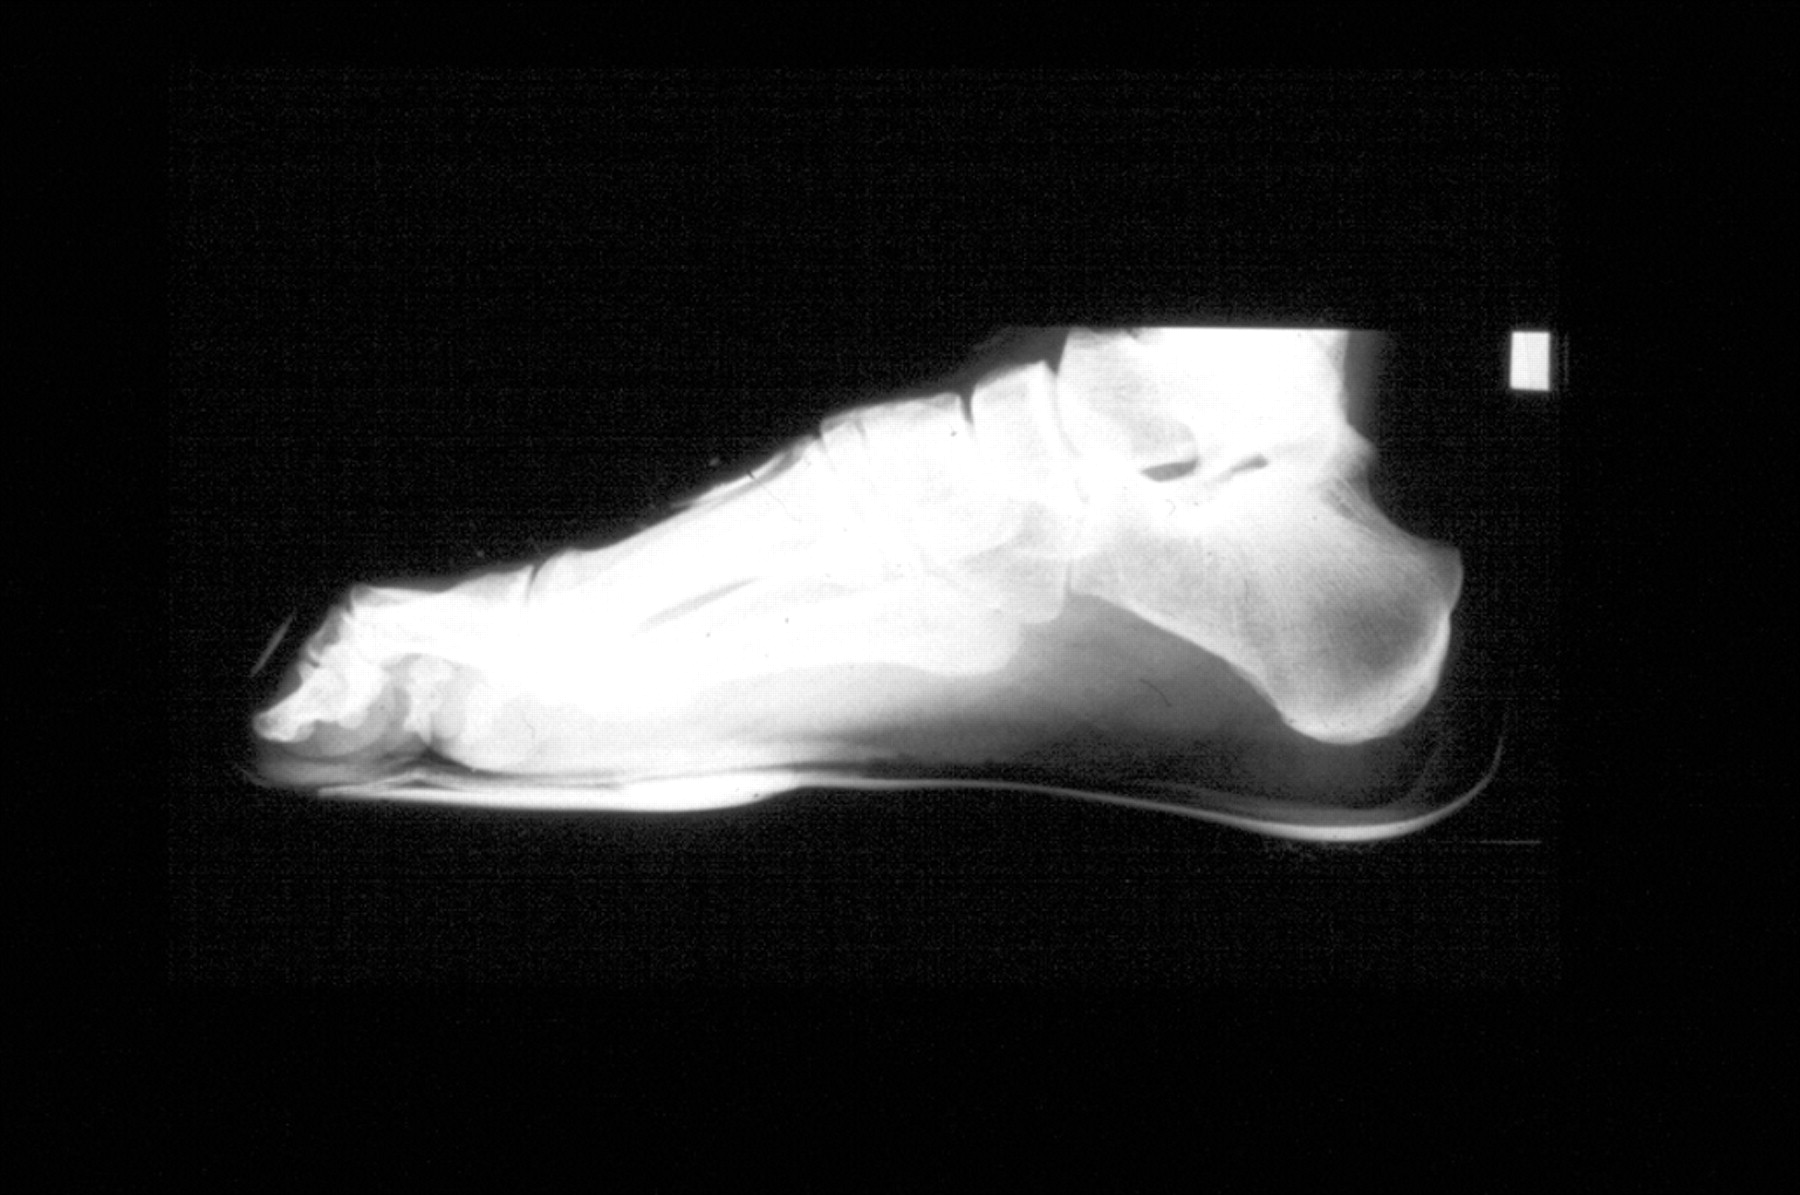

Foot and shoe Xray, 1896 Stock Image C034/5128 Science Photo Library Climbing Shoe Xray Supinated (high arch) foot with clawed toes. The same climber in a climbing shoe. The shoes i bought were: One person can love a shoe while another may hate it. We put a dozen pairs of climbing shoes to the test on boulder problems, sport climbs, and traditional routes. The climber’s barefoot while standing. If you have space in your. Climbing Shoe Xray.

X ray of a foot hires stock photography and images Alamy Climbing Shoe Xray Clawed toes and hallux valgus. Supinated (high arch) foot with clawed toes. Take a look at the findings below. The same climber in a climbing shoe. The same climber in a climbing shoe. We put a dozen pairs of climbing shoes to the test on boulder problems, sport climbs, and traditional routes. The climber’s barefoot while standing. The shoes i. Climbing Shoe Xray.